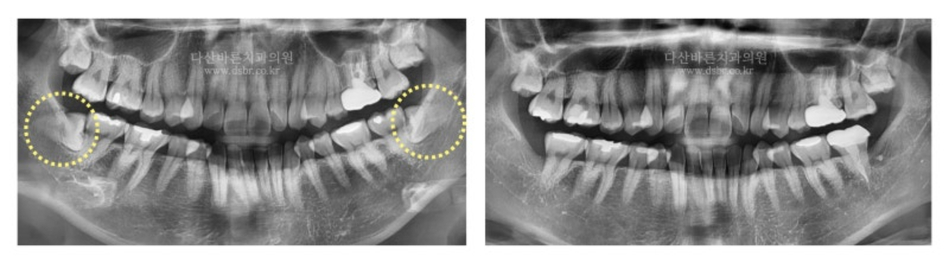

CASE 2.

Đó không phải là trường hợp đơn giản vì răng khôn nằm ngang và hơn 2/3

trong số đó bị ảnh hưởng bởi xương nướu. Đây là trường hợp một lượng nhỏ xương nướu

bị loại bỏ đồng thời phần đầu và chân răng được chia ra và nhổ bỏ hai lần.

CASE 3.

Đây là trường hợp răng khôn nằm ngang và bị ảnh hưởng sâu hơn một chút.

Đây là trường hợp cần phải lấy xương cầu kỳ hơn vì răng khôn đã mọc hoàn toàn vào xương nướu.